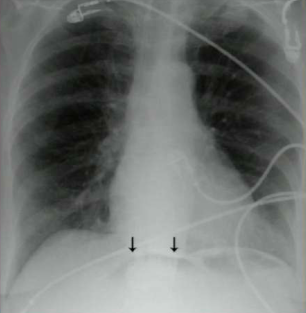

What does this patient have?

Ascities. Note increased density, central bowel loops, thickened peritoneal fat stripe, loss of other edges (liver, spleen and bladder)